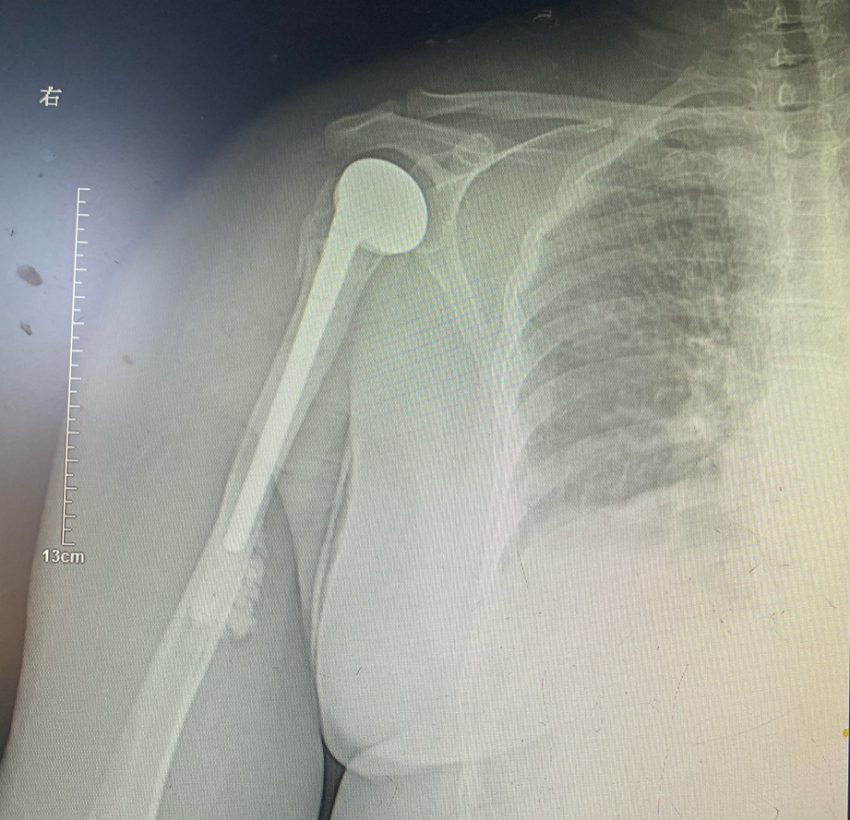

鉴于患者既往身体素质较好,为确保以后的生活质量,经过全科医师反复讨论,决定行右肩关节置换手术,尽可能减少骨折后遗症,最大限度恢复肩关节功能。确定手术方案后,经过周密的术前设计和准备,在麻醉科和骨科医护人员的密切配合下,顺利为患者实施手术。术后X片、CT复查显示假体位置良好,对位对线准确,松紧度适宜。目前患者能在医师指导下逐步进行康复锻炼,肩关节活动明显改善,患者对手术十分满意。经过康复训练,患者右上肢功能也将逐步恢复到健肢水平。

人工肩关节置换术在治疗肩关节骨性关节炎、类风湿性关节炎、肱骨近端粉碎性骨折、肱骨头缺血性坏死、无法修复的肩袖撕裂等疾病治疗方面具有重要的地位。不同于髋膝关节置换,该手术过程非常困难,如何适度松解关节囊并使关节脱位,如何充分暴露并保护臂丛神经及血管不受医源性损伤,完成肩袖修补,对术者有较高要求,操作难度较大。